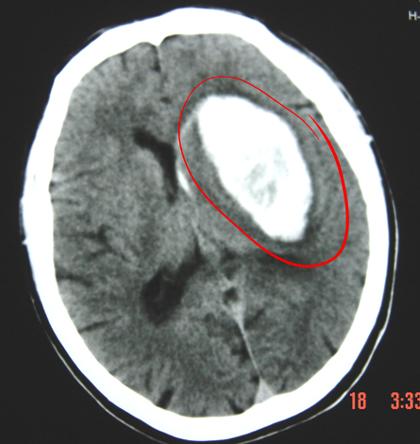

丘脑出血ct图片解说图

丘脑出血ct图片解说图,脑出血ct图片解说图

典型病例二: 左侧丘脑出血破入脑室系统

丘脑出血破入脑室

丘脑出血——内囊内侧型出血